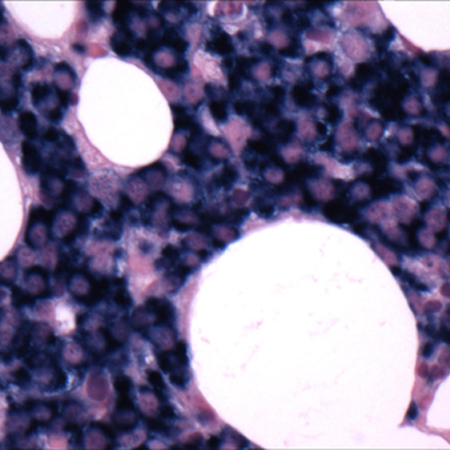

[Figure caption and citation for the preceding image starts]: Bone marrow biopsyCourtesy of Dr Robert Hasserjian, Hematopathology, Massachusetts General Hospital; used with permission [Citation ends].

[Figure caption and citation for the preceding image starts]: Bone marrow biopsy after histochemical analysis for kappa light chainCourtesy of Dr Robert Hasserjian, Hematopathology, Massachusetts General Hospital; used with permission [Citation ends].

[Figure caption and citation for the preceding image starts]: Bone marrow biopsy after histochemical analysis for lambda light chainCourtesy of Dr Robert Hasserjian, Hematopathology, Massachusetts General Hospital; used with permission [Citation ends].

[Figure caption and citation for the preceding image starts]: Aspirate showing plasma cell infiltrateCourtesy of Dr Robert Hasserjian, Hematopathology, Massachusetts General Hospital; used with permission [Citation ends].